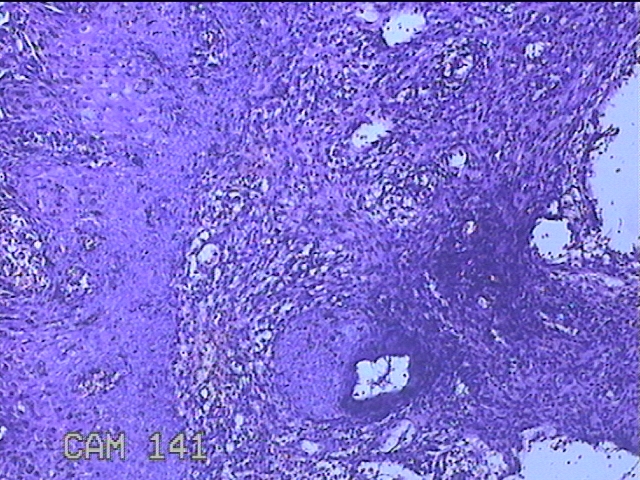

宫颈3点、9点、11点、12点组织

性别

女

年龄

37岁

临床诊断

人乳头瘤病毒感染

一般病史

HPV其他12型阳性

标本名称

大体所见

1.“宫颈3点组织”:灰白粉红色组织1x0.8x0.2cm一块。 2.“宫颈9点组织”:灰白粉红色组织0.7x0.5x0.2cm一块。 3.“宫颈11点组织”:灰白粉红色组织0.8x0.5x0.2cm一块。 4.“宫颈12点组织”:灰白粉红色组织8.5x0.5x0.2cm一块。